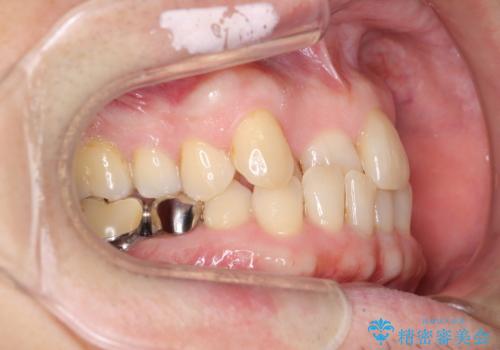

矯正治療後、右下のインレーブリッジおよび左下の銀歯のやりかえを行なっています。

右上の八重歯は、右上の奥歯を矯正用ミニスクリューを用いて遠心移動を行い解消しました。

下の前歯はIPR(エナメル質を薄く削り歯を小さくする処置)を行なっています。